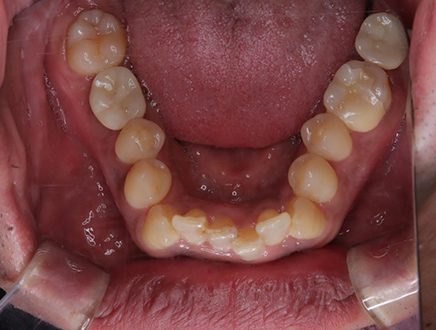

| 治療部位 | 両側下顎臼歯部 |

|---|---|

| インプラント本数 | 1本ずつ |

| 単価 | 40万円/本 |

| 合計費用 | 40万円 |